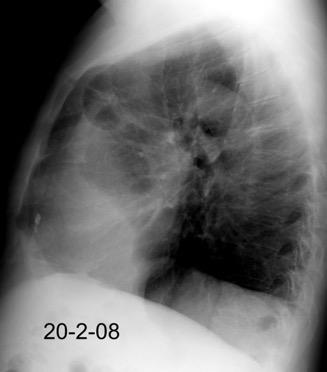

Neumonía a neumococos base izda. con derrame que aumenta.

Broncograma en lateral y en US.

(36-66% en ingresados)